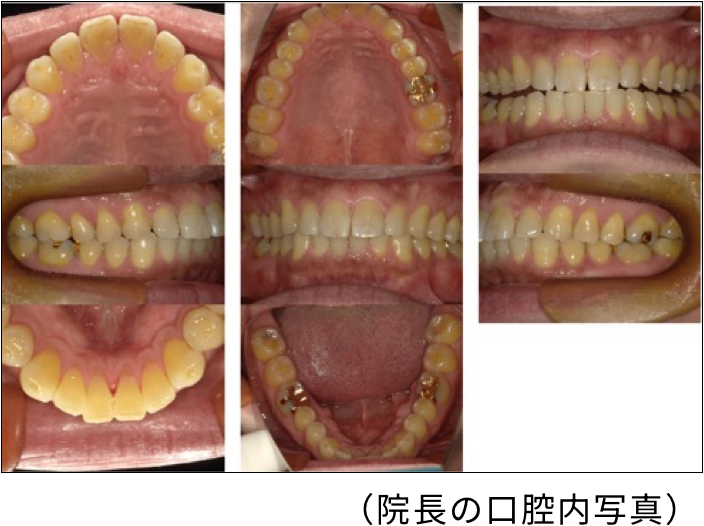

口腔内写真

◎口腔内写真で確認できること

● 上下かみ合わせの関係と歯並びの状態

● 歯の色調や形態

● 歯ぐきの状態

● プラークコントロールの状態

● 小帯の付着異常

● 矯正治療中の歯の移動状態

● 治療による詳細な変化

口腔内写真のメリット★

● 限られた診療時間内で直接口の中を診るだけでなく、撮影された画像を見返すことにより、詳細な状態や変化をしっかり確認できるため、治療の精度を上げることができる。

● 患者さんにご自身のお口の中の写真を過去と現在の状態を比べて見ていただくことにより、治療への理解を深めていただくことができる。

わかりやすさのために院長の色々な写真を載せましたが、患者さんの写真はすべて個人情報として厳重に管理しており、治療以外の目的で使用することは一切ありません。どうかご安心ください。